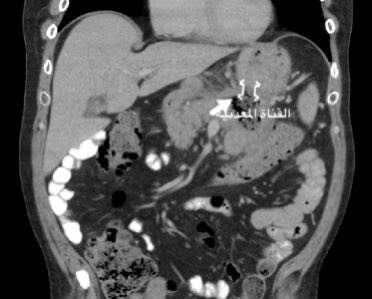

#مرض_من_العيادة (سلسلة توعوية اسبوعية)    مريض في ال ٥٠ من العمر يعاني من الم وانتفاخ في اعلى البطن. يشرب الخمور. سبق علاجه من التهابات البنكرياس النا